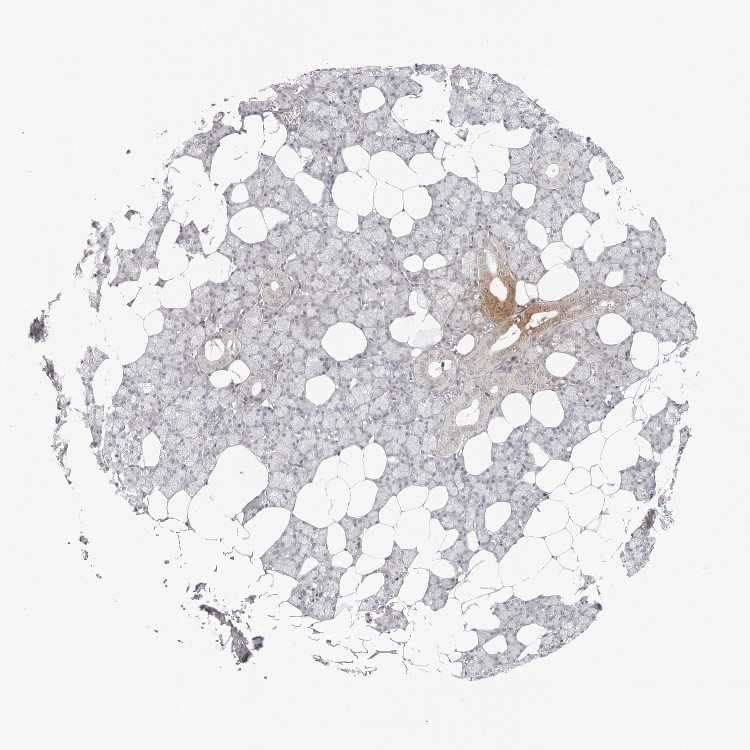

SALIVARY GLAND - Antibody stainingi

Antibody staining in the annotated cell types in the current human tissue is reported as not detected, low, medium, or high, based on conventional immunohistochemistry profiling in selected tissues. This score is based on the combination of the staining intensity and fraction of stained cells.

Each image is clickable and will lead to virtual microscopy that enables deeper exploration of all samples and also displays staining intensity scores, fraction scores and subcellular localization as well as patient and tissue information for each sample.

Antibody HPA003351Antibody HPA003355Antibody CAB021892

Glandular cells LowMediumNot detected